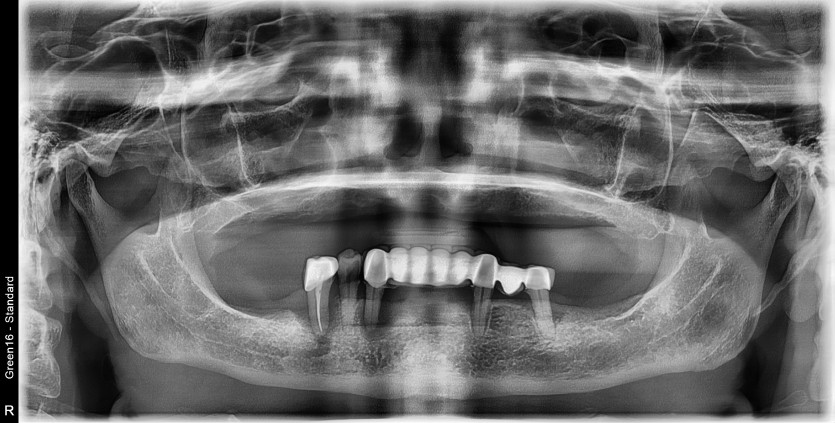

전체 임플란트 증례입니다.

16개의 임플란트로 완성하였습니다.